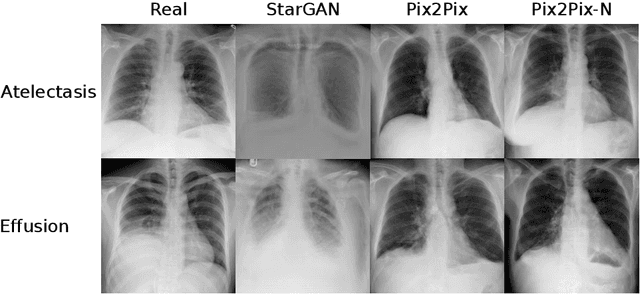

Recent works show that Generative Adversarial Networks (GANs) can be successfully applied to chest X-ray data augmentation for lung disease recognition. However, the implausible and distorted pathology features generated from the less than perfect generator may lead to wrong clinical decisions. Why not keep the original pathology region? We proposed a novel approach that allows our generative model to generate high quality plausible images that contain undistorted pathology areas. The main idea is to design a training scheme based on an image-to-image translation network to introduce variations of new lung features around the pathology ground-truth area. Moreover, our model is able to leverage both annotated disease images and unannotated healthy lung images for the purpose of generation. We demonstrate the effectiveness of our model on two tasks: (i) we invite certified radiologists to assess the quality of the generated synthetic images against real and other state-of-the-art generative models, and (ii) data augmentation to improve the performance of disease localisation.